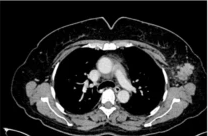

To further increase the specificity and sensitivity of PET, researchers suggested combining CT and PET. FDG-PET/CT is used to estimate the therapeutic response of the tumor, detect recurrence or distant metastasis, and detect tumors in the early stage. Additionally, FDG-PET/CT can locate metastasis in unexpected locations (28). A prospective evaluation conducted by Shawky et al. (28) found that PET/CT was able to detect contralateral lesions in two patients (Figure 2), which traditional CT imaging could not detect. Moreover, PET/CT imaging could detect lesions in the bone marrow which was not detected by CT imaging as well (28). Several studies have shown that PET/CT can detect additional lesions than those detected by CT, and it can detect unsuspected distant metastasis in just one whole body scan (29, 30). Bone metastasis is the most common site of breast cancer metastasis. Both CT and PET/CT can detect osteoblastic, osteoclastic, and mixed bone metastases with the same sensitivity and the same specificity (28). However, PET/CT can detect bone metastasis earlier than CT and can detect bone infiltration that cannot be seen with traditional CT imaging. Additionally, it can detect the resolution of bone infiltration before the appearance of definitive signs of healing (28).

Figure 2: Detection of contralateral breast cancer using PET/CT (28).